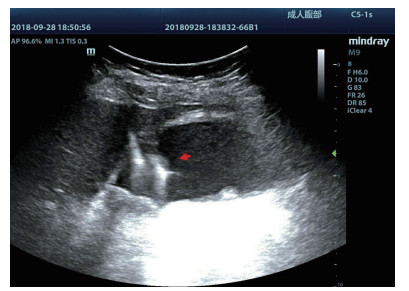

均采用塞丁格(Seldinger)技术置入引流管(图 4):穿刺穿刺点的选择①左侧卧位,超声确定胆囊床方位,取腋前线肋间或肋缘下进针; ②经肝的路径长度应大于2.0 cm胆囊穿刺点为中上部距离胆囊颈约1 /3的位置; ③穿刺路径上尽量避开大血管及大胆管结构; ④结合术前经肘静脉超声造影情况,避开胆囊穿孔部位及周边黏连组织。操作过程:由超声介入治疗组专业医师单人操作,为获得更自由的穿刺角度以及在穿刺过程中根据患者呼吸活动随时对进针角度进行调整,本组操作均未使用超声探头引导架。操作步骤①常规碘伏皮肤消毒,2%利多卡因局部麻醉至肝脏被膜。操作医师一手持超声探头,清晰显示进针入路,一手持18 G PTC穿刺针经皮经肝由胆囊床穿刺进入胆囊,拔出针芯,可见胆汁自行流出或用20 mL注射器回抽见胆汁。②沿针鞘置入导丝,超声探查见导丝进入胆囊,拔出针鞘。③扩张器扩张针道。④根据抽出胆汁的混浊程度,沿导丝置入合适型号的引流管,确定引流管通畅后拔出导丝,拉紧猪尾导管的外置固定线,使导管弯曲头牢固卷曲,形成内固定,皮肤缝线外固定引流管,双重固定更加有利于引流管留置于可靠位置,有效避免脱管。术后再次皮肤消毒,覆盖无菌贴膜。接引流袋。⑤术中及术后半h均予心电监测,术后常规送胆汁细菌培养,密切观察患者症状体征改善情况。

| 图 4 胆囊置管过程,导丝进入胆囊腔内(箭头处) |

2 结果33例均顺利完成超声引导下PTGBD,其中术前静脉路超声造影诊断2例胆囊穿孔局限性胆汁性腹膜炎,先经腹腔穿刺抽吸胆囊周围积液,再经皮经肝穿刺胆囊。置管成功后,经静脉团注声诺维超声造影剂2.0 mL,其中1例注射造影剂注10 s后,于穿刺处的肝脏表面见高回声造影剂持续向肝外溢出,同时见肝肾间隙、右侧髂窝造影剂聚集且逐渐增多。遂于急诊行腹腔镜探查止血成功。其余32例无明显造影剂溢出或仅为极少量溢出且无动态增多趋势,评估为穿刺后无活动性出血。置管成功后快速抽出胆囊内残留胆汁,减轻胆囊压力后,在超声造影模式下直接经引流管注入配制待用的稀释声诺维造影剂20 mL,实时动态的观察造影剂在胆囊腔内的充盈范围,观察胆囊周边及腹腔内有无造影剂外渗,其中3例(9.1%)出现不同程度的造影剂外渗。均为自胆囊床处渗入肝肾间隙,同时伴随着患者腹痛症状加剧,立即予改变体位(头高脚底位,减轻膈肌刺激)及镇痛处理,其中1例渗出量较大者出现明显急腹症表现伴有血压降低,予行急诊剖腹探查+胆囊切除+腹腔冲洗术,术中见胆囊为系膜胆囊,腹腔内见褐色胆汁样积液,予行胆囊切除+腹腔冲洗术,术后生命征平稳,抗感染及腹腔引流后病情稳定出院。住院期问未发生胆囊引流管脱落事件。全部患者穿刺引流后继续给予抗感染等治疗,腹部症状明显好转,体温逐渐正常,血白细胞有明显下降趋势,其中102例患者胆囊炎症及全身情况逐渐好转后择期出院。除中转腹腔镜手术2例外,其余31例患者于PTGBD后4 h内疼痛均减轻,从术前(6.0±1.4)分,术后4 h降至(4.2±1.0)分,术后24 h为(3.1±0.9)分; 术后(33.0±3.6)h体温降至正常,(34.6±6.8)h白细胞计数正常,(38.4±3.3)h中性粒细胞百分比正常,术后(1.6±1.0)d恢复饮食,其中29例患者胆囊炎症及全身情况逐渐好转后于术后(6.8±1.3)d出院,2例患者住院期间临床死亡,死亡原因为肺部感染1例(3.0%)、心功能不全1例(3.0%)。所有病例未出现与穿刺有关的气胸、腹腔出血、胆道出血、胆漏、胃肠道损伤等并发症,穿刺抽取胆汁培养,23例(69.7%)胆汁细菌培养呈阳性,其中大肠埃希菌19例(82.6%),克雷伯菌属4例(17.4)。